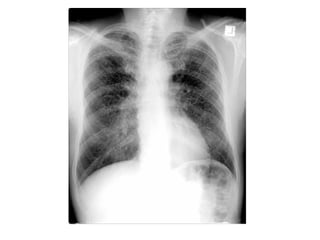

2-Interstitial Fibrosis (Asbestosis) :

-Features on chest radiographs include ground-glass

opacification, small nodular opacities, “shaggy” cardiac

silhouette, and ill-defined diaphragmatic contours, it has

been reported that 80% of patients with asbestosis have

coexistent pleural disease at chest radiography, fibrous

bands are sometimes seen to radiate inward from the

pleura

PA radiograph shows diffuse fine nodular and reticular opacification

with irregularity of mediastinal and diaphragmatic contours, the

costophrenic angles are blunted because of pleural thickening